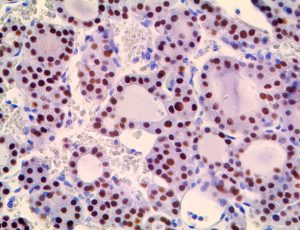

It is the ICU physician who is most likely to witness one of the deadliest manifestations of the abnormal immunological response, the cytokine storm syndrome (CSS). This response is also referred to by some as the cytokine release syndrome (CRS). CSS is characterized by continuous activation and expansion of macrophage and lymphocyte populations, which secrete large amounts of cytokines, causing the cytokine storm. This massive cytokine release is akin to hemophagocytic lymphohistiocytosis (HLH) disease, a syndrome characterized by initial unchecked and persistent activation of cytotoxic T lymphocytes and NK cells.

Clinical and laboratory manifestations of HLH include fever, enlarged liver and/or spleen, neurologic dysfunction, coagulopathy, liver dysfunction, cytopenias (i.e., low levels of erythrocytes, leukocytes, and/or platelets), hypertriglyceridemia, hyperferritinemia, hemophagocytosis, and eventually diminished NK cell activity as the immune system becomes progressively paralyzed. HLH can be familial (primary HLH) or secondary to another disease process (sHLH), such as rheumatic disease, in which it is referred to as macrophage activation syndrome (MAS, characterized by elevated ferritin).